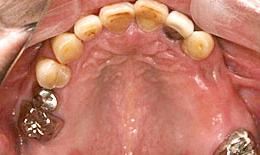

治療後

上顎

インプラントを2本埋め込んで、セラミックスクラウンを被せた

下顎

インプラントを4本埋め込んで、セラミックスクラウンを被せた